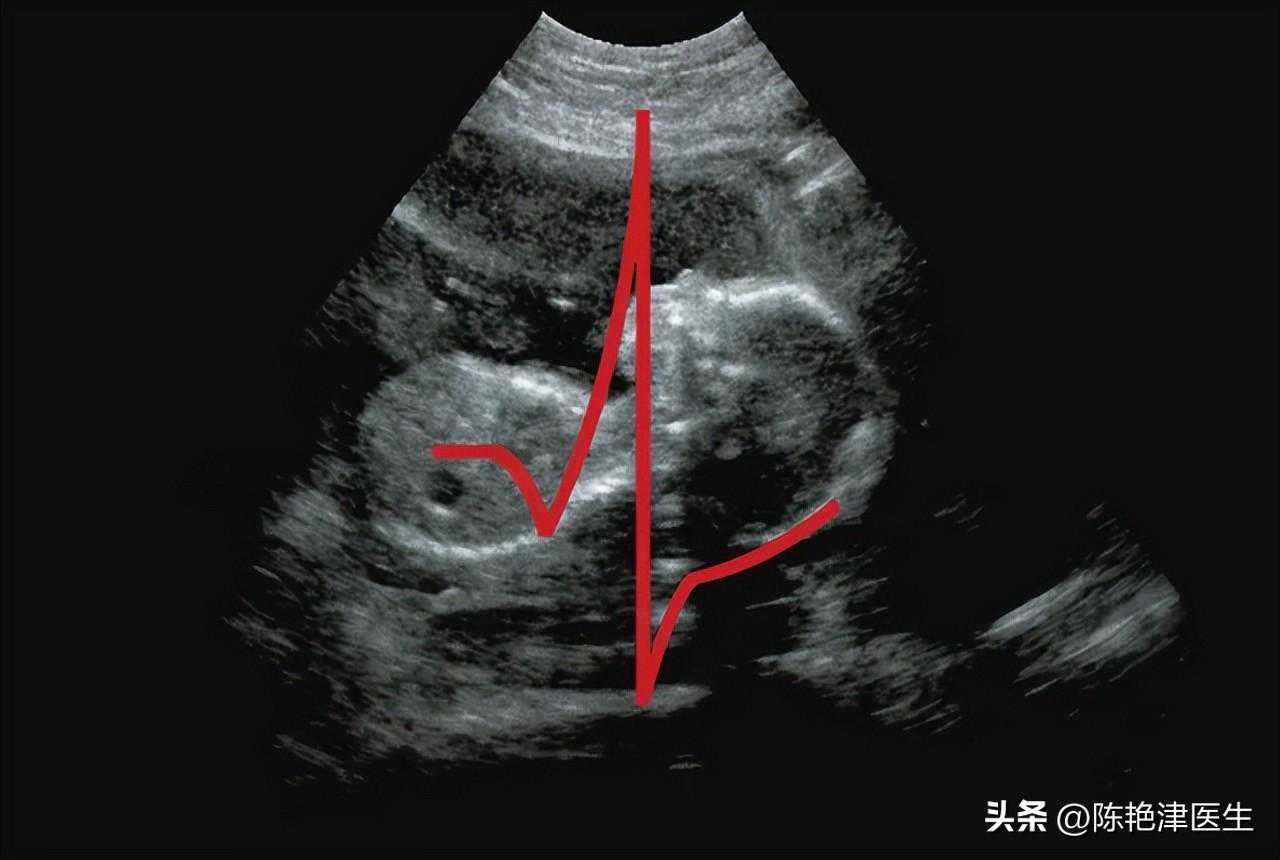

心电图和超声心动图都是诊断心脏功能的重要工具,但它们的工作原理和提供的信息各有侧重。超声心动图通过声波技术生成心脏图像,能够更深入地揭示心脏结构的细节,包括心脏瓣膜、心室和心房的大小及功能状况。

在心脏结构异常、心肌病和心脏瓣膜病等方面,超声心动图更胜一筹。

有些心脏疾病确实会导致心脏电活动的变化,但也有部分疾病仅影响心脏结构,而不影响心电表现。

例如,心脏扩大、收缩功能减弱或心脏瓣膜关闭不全,这类病变往往不会随着症状的缓解而自动改善,可以随时进行超声心动图检查以持续监测心脏状况。

心率加快时,超声心动图的具体表现可能因个体差异和潜在病因的差异而有所不同。在超声心动图的观察下通常表现为心脏的运动节奏显著增强。

由于心率加速,心脏的泵血功能也会相应提升,进而改变血流的动力学特性。在超声心动图的呈现中,这种变化可能直观地表现为血流速度的显著提升,有时甚至在特定情况下会出现血流的湍流或涡流现象。

此外,为了满足身体对血液需求的增加,心率加快时心脏每分钟输出的血量也可能有所增加。

相比其他检查项目,超声心动图技术具有诸多优势。它安全无创,不会对患者造成任何伤害;同时,其造价相对较低,使得更多患者能够负担得起这项检查。此外,超声心动图的结果可靠,床旁检查方便,可重复性高,因此备受临床医生的青睐。